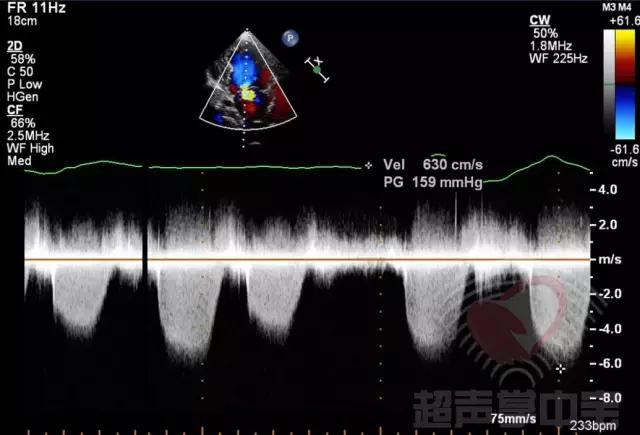

二尖瓣充血性囊肿,二尖瓣血性囊肿是什么意思 图8:CW于囊状物内探及收缩期负向高速湍流,流速6.3m/s,压差159mmHg